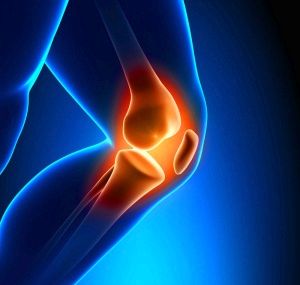

Остеохондроз колінного суглоба, наприклад, зустрічається досить часто особливо у віковому проміжку від 15 до 30 років. Хоча більшість звертаються за допомогою пацієнтів є чоловіками, такі дегенеративні зміни можуть спостерігатися також і у жінок.

Основним ознаками наявності патології і необхідності провести лікування остеохондрозу колінного суглоба є сильний больовий синдром. Так як подібні ознаки можуть вказувати на ряд інших захворювань, при збиранні анамнезу звертають увагу також на такі характерні прояви:

- Больовий синдром має постійно зростаючу інтенсивність. Час між нападами постійно скорочується. Зростає інтенсивність хворобливих відчуттів.

- Рухливість. У міру розвитку патології спостерігається збільшення обмеження колінного суглоба, що відбивається на ході пацієнта. Деформуючий остеохондроз колінних суглобів постійно прогресує і при ігноруванні симптомів призводить до його повної нерухомості.

- Запальний процес. Характеризується локальним поширенням. Як правило, спостерігається постійний розвиток запального процесу.